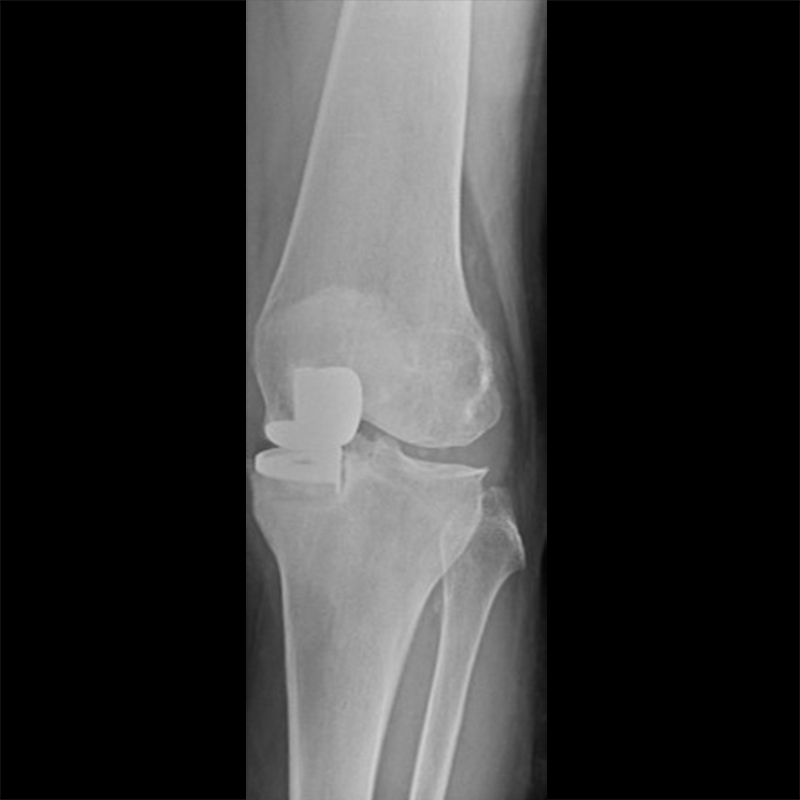

外院失敗本院再置換 首頁 案例分享 膝關節手術 外院失敗本院再置換 蕭女士 69歲 術前 術後 81歲 林女士 術前 術後 蕭女士 69歲 術前 術後 鄒女士 69歲 術前 術後 李女士 74歲 術前 術後 吳女士 71歲 術前 術後 謝女士 65歲 術前 術後